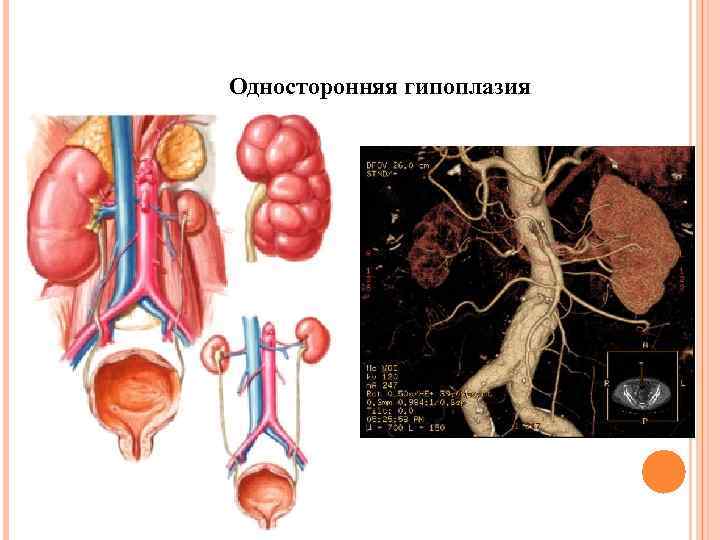

Односторонняя гипоплазия

Односторонняя гипоплазия

Односторонняя гипоплазия

Односторонняя гипоплазия